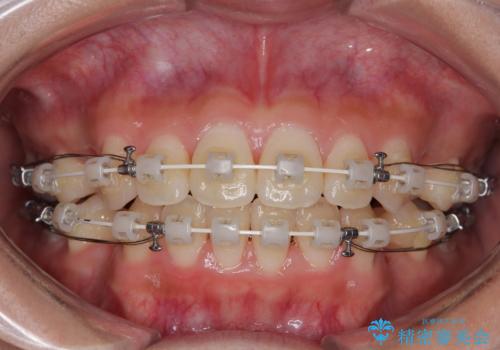

- 審美装置

- 1年10ヶ月

単純に上下左右の第一小臼歯4本を抜歯して口元の突出感を改善することも考えられましたが、上顎骨よりも下顎骨の幅が広いため、より良い咬み合わせを達成することを目的として、急速拡大装置を用いて上顎骨を拡大することとしました。

歯列矯正では基本的に骨格を改善することはできませんが、急速拡大装置(MARPE)を使用することで上顎骨を側方に拡大させることができ、咬合状態を大きく改善することができます。